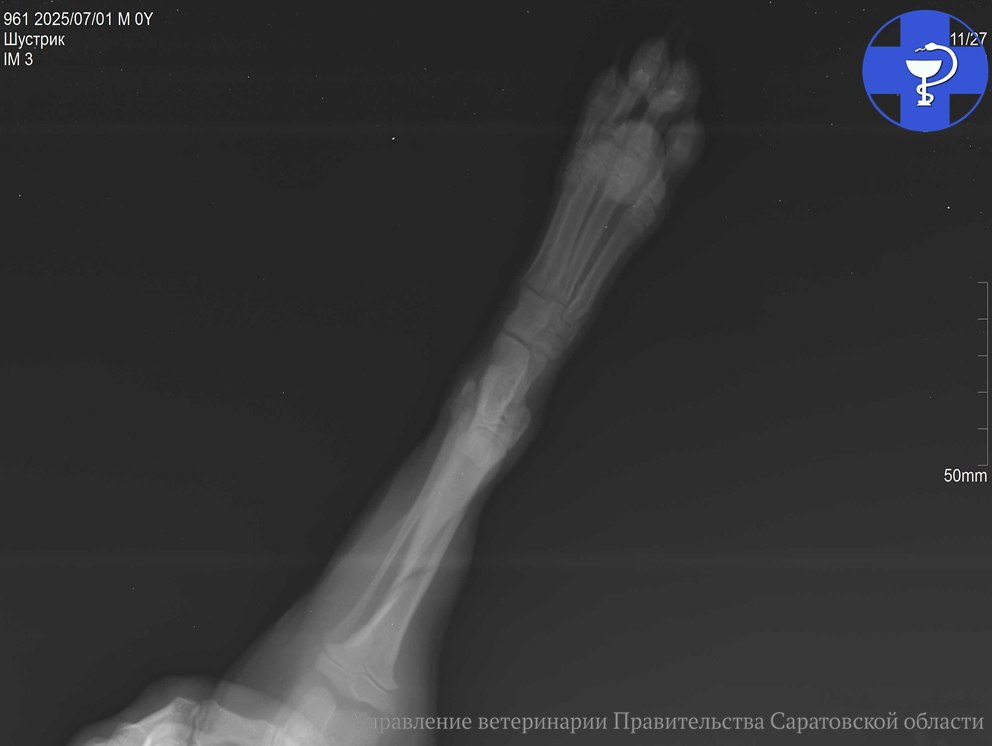

После осмотра ветеринар назначил рентген-диагностику, которая выявила косой оскольчатый перелом большеберцовой кости. Она является одной из основных костей голени у собак, обеспечивающая поддержку и движение.